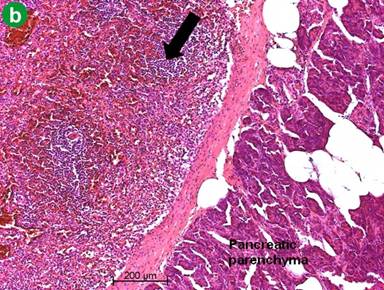

Postoperative histological examination of the resected specimen or taken biopsies revealed pancreatic metastases of extrapancreatic malignomas (Figure 1) in 8 patients (renal cell carcinoma, n=3; melanoma, n=2; duodenal gastrinoma, n=1; breast cancer, n=1; retroperitoneal liposarcoma, n=1). In 10 patients (52.6%) the following rare benign tumors were detected: solid pseudopapillary tumor of the pancreas (n=3) (Figure 2), mature teratoma of the pancreas (n=2) (Figure 3), capillary hemangioma of the pancreas (n=1) (Figure 4), intrapancreatic accessory spleen (n=1) (Figure 5), lymphoepithelial cyst of the pancreas (n=1) (Figure 6), hamartoma of the pancreas (n=1) (Figure 7), and pancreatic sarcoidosis (n=1). In one patient an advanced yolk sac tumor of the pancreas with peritoneal carcinosis was diagnosed (Table 2).

Figure 5. Intrapancreatic accessory spleen (arrow). a. Macroscopic photograph. b. Histology of an accessory intrapancreatic spleen with red and white pulpa (arrow) with a fibrous capsule next to normal pancreatic tissue (H&E-staining). |